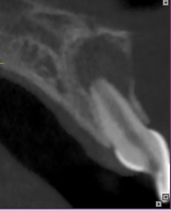

Tomografía axial computarizada (TAC): imagen hipodensa con pérdida de la cortical externa en zona apical de incisivos centrales superiores y reacción perióstica asociada (Figura 1).